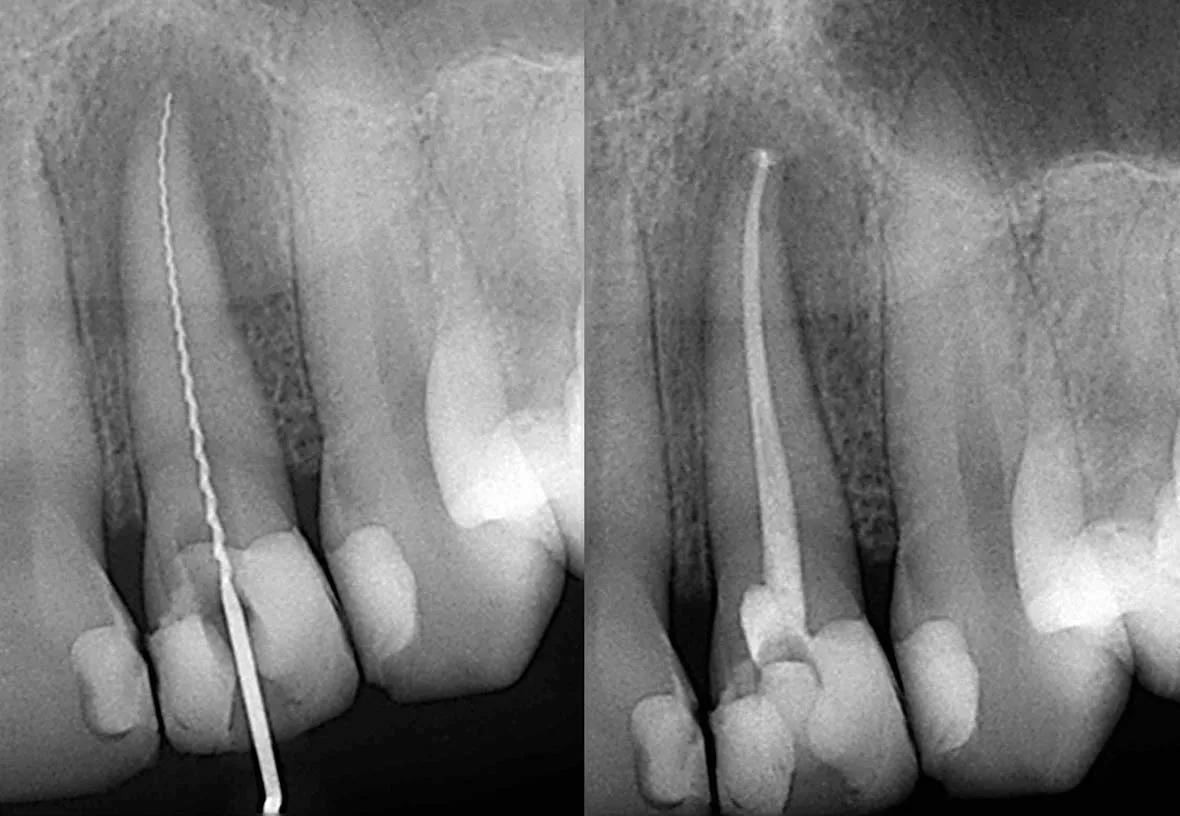

Root canal treatment involves the removal of the soft inner tissue of the tooth, also called the pulp. Your dentist will drill a tiny hole in the affected tooth and remove the pulp using special tools. After the pulp is removed, your dentist will clean the inside of the tooth to prevent further infection, fill the tooth with material, and seal the hole with a filling. After the procedure, your dentist will restore the tooth with a temporary dental crown while a permanent crown is being made.